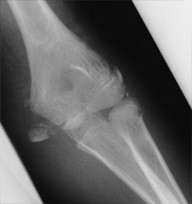

Capitulum Fracture